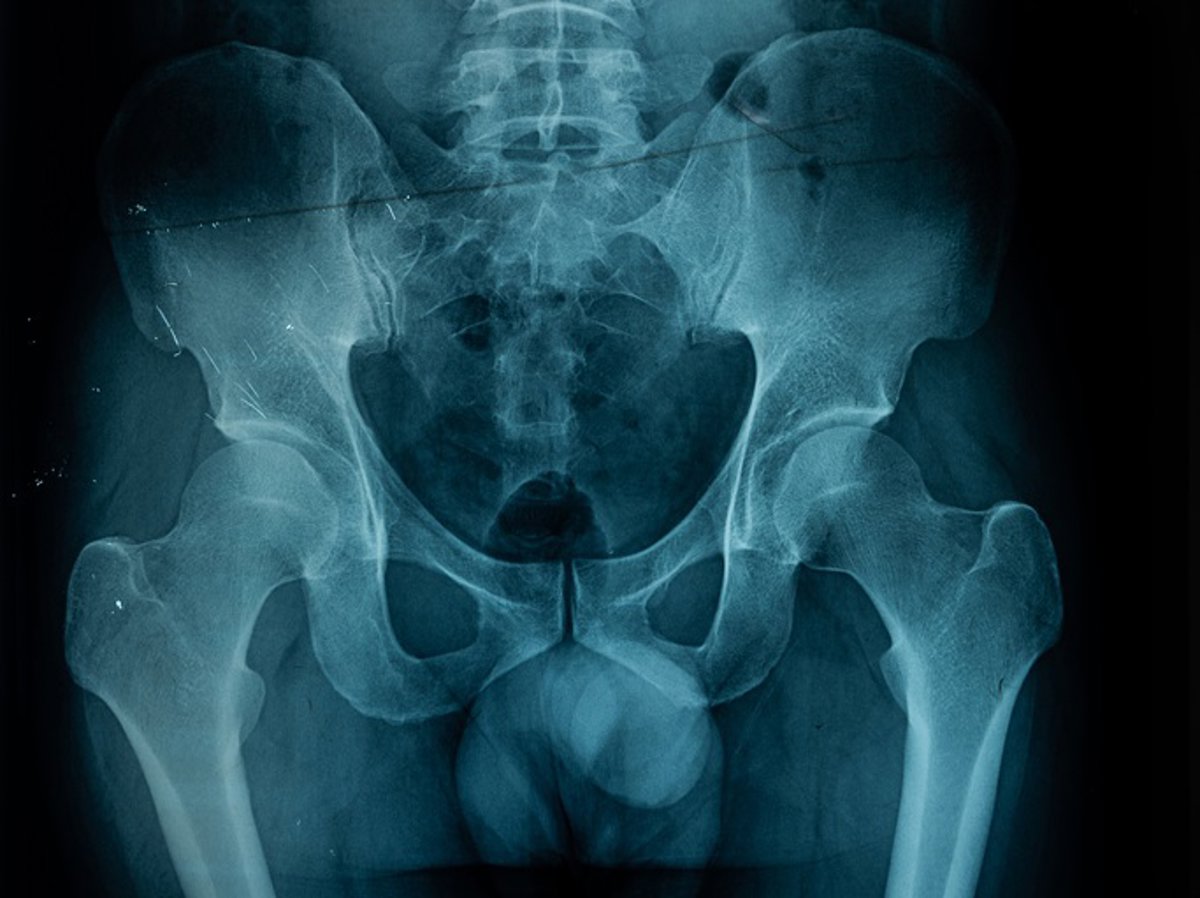

Archivo - Arquivo - Radiografia da pelve

KOOL99/ ISTOCK - Arquivo